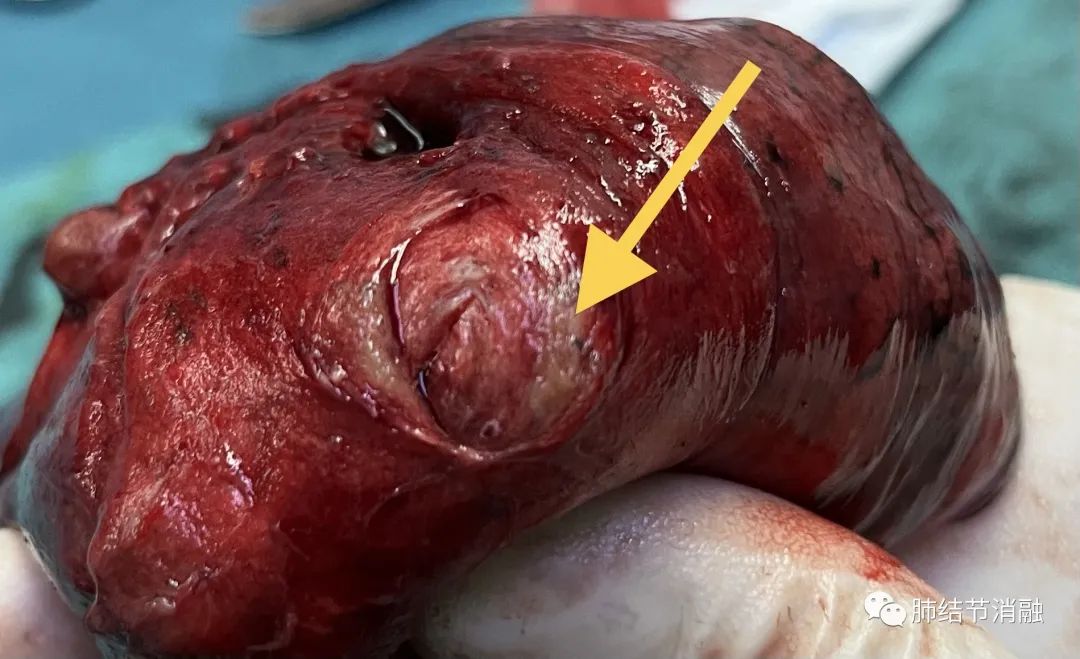

次要病灶1染色区域

次要病灶1 5毫米结节